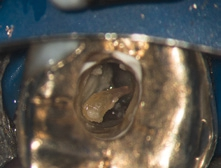

- Obliterationen/Dentikel (Abb. 7–9),

Bei der IKD wird bereits mit Feilen geringster ISO-Größe überprüft, ob es möglich ist, den apikalen Bereich eines Kanalsystems zu erschließen. Vor der maschinellen Aufbereitung liefert die Etablierung eines Gleitpfades wichtige taktile Informationen über die Kanalanatomie und erzeugt den definierten Weg, dem die maschinellen Instrumente vorhersagbar folgen können. Für die meisten maschinellen Systeme eignet sich ein Gleitpfad, bei dem zum Ende der Handsondierung eine ISO-15-Handfeile ohne Widerstand in den Kanal eingebracht werden kann. Ein gleichmäßiger, stufenloser Gleitpfad begünstigt eine erfolgreiche suffiziente und vollständige maschinelle Aufbereitung. Spätestens jetzt sollte mittels elektrometrischer Messung die Arbeitslänge festgelegt und mit einer sogenannten Messaufnahme röntgenologisch überprüft werden. Die Frage „Welches maschinelle Aufbereitungssystem ist nun das richtige?“ soll und kann hier nicht besprochen werden, da deren Beantwortung den Umfang des Artikels sprengen würde. Es ist jedoch dringend zu empfehlen, die für jedes System angebotenen Kurse zu besuchen, um sich mit dem jeweiligen Instrumentensystem vertraut zu machen und zu entscheiden, ob es sich in den persönlichen Arbeitsablauf nahtlos integrieren lässt.